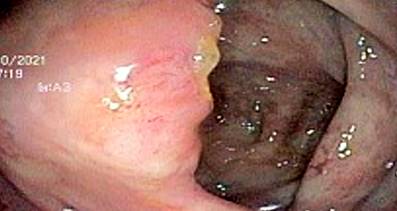

The treating clinicians decided to start the search for the gastrointestinal etiology of eosinophilia associated with gastrointestinal symptoms presented by the patient. First, he underwent an endoscopy in which moderate erythematous gastritis (histopathological examination: mild superficial chronic gastritis, without Helicobacter pylori, atrophy, or intestinal metaplasia) and nonspecific duodenitis (histopathological examination: mild chronic duodenitis with intraepithelial lymphocytes 8-10/100 epithelial cells, without typical findings of a specific disease) were found. Then, he underwent a colonoscopy that presented the following findings: in the distal ileum, from approximately 15 cm from the ileocecal valve to the distal, marked mucosa congestion was observed with “punched” erosions, punctate erythema, and loss of mucosal vascularization (Figure 1). On histopathological examination, moderate chronic ileitis was found with no specific findings. In the cecum, at the level of the ileocecal valve and proximal to the appendicular orifice, erythema of the mucosa and partial loss of mucosal vascularization were observed (Figure 2). There was a significant increase in eosinophils at the level of the lamina propria and crypts, which reached approximately > 200 eosinophils in a high-power field in the histopathological examination (Figures 3 and 4). This eosinophilic infiltrate was also accompanied by plasma cells, scarce lymphocytes, and cryptic abscesses, which are findings related to eosinophilic colitis.

Endoscopic findings in patients with eosinophilic colitis are nonspecific. In fact, they may have a normal appearance in up to 70% of cases, so there may be overlap with diarrhea predominant-irritable bowel syndrome (IBS-D), as described by the study by Carmona-Sánchez et al.,16 which found a prevalence of 4.7% of patients with eosinophilic colitis who had also been diagnosed as IBS-D. Other common manifestations include erythema, edema, decreased mucosal vascularization, erosions, and ulcers. Regarding the location of the lesions, they can be found more frequently in the right and left colon and as pancolitis in up to 11% of cases.6 In our case, there were findings both in the distal ileum (“in punch” erosions, erythema, loss of mucosal vascularization) and in the cecum (erythema and loss of mucosal vascularization). In the other colon segments, there may have been the eosinophil counts necessary to diagnose eosinophilic colitis. However, the required samples were not obtained.